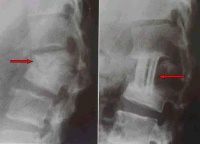

图片说明:左图为治疗前二维CT,右图为微创治疗后3年半

随访二维CT照片。